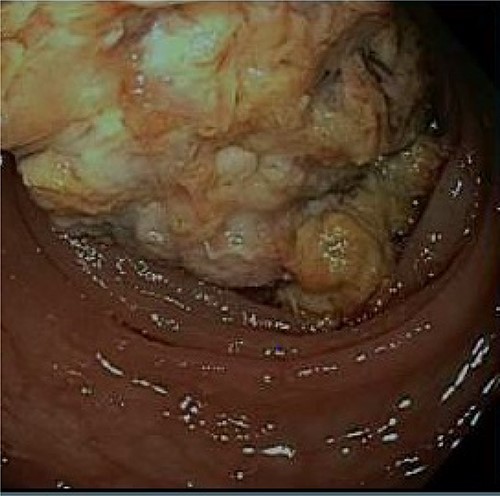

After discharge, the patient continued to experience intermittent abdominal pain, melena and diarrhea. These symptoms prompted three more emergency room visits over a 1-month period. Repeat abdominal imaging (CT scan) revealed previously noted colonic inflammation. In addition, colonic intussusception was noted this time. The patient underwent a colonoscopy 2 weeks later revealing a fungating partially obstructing descending colon mass acting as the lead point for intussusception (Fig. 3). The mass was deemed too large for endoscopic removal and multiple biopsies were obtained. These biopsies revealed necrotic granulation tissue without any evidence of malignancy. Patient subsequently underwent an uneventful laparoscopic left hemicolectomy and was discharged home on postoperative Day 3. Final pathology revealed moderately differentiated adenocarcinoma, invading into pericolonic adipose tissue and metastases in 3 of 48 lymph nodes. Immunohistochemistry analysis revealed absence of MLH1, PMS2 and MSH and presence of PSH2, concerning for Lynch Syndrome. Further testing of MLH1 promoter was negative for hypermethylation. The patient was referred to medical oncology for adjuvant chemotherapy. She remains disease free and is on active surveillance for colorectal cancer in setting of Lynch Syndrome.

A fungating partially obstructing mass was found in the descending colon on colonoscopy.